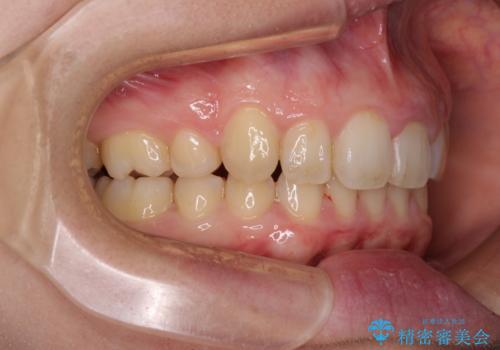

- 八重歯を気にして来院された患者様です。

八重歯の後ろの歯を1歯抜歯し、補助装置(リンガルアーチ)を用いて八重歯の位置を改善し、その後インビザラインにより矯正治療を行うこととしました。

下顎前歯が1本欠損したスリーインサイザーという状態であるため、上下の前歯の咬み込みが深くなったり、奥歯の咬み合わせが理想的なものとならなかったりという仕上がりになってしまいます。

前歯の見た目や奥歯の咬み合わせに、患者様が違和感を感じない状態として治療を終えました。